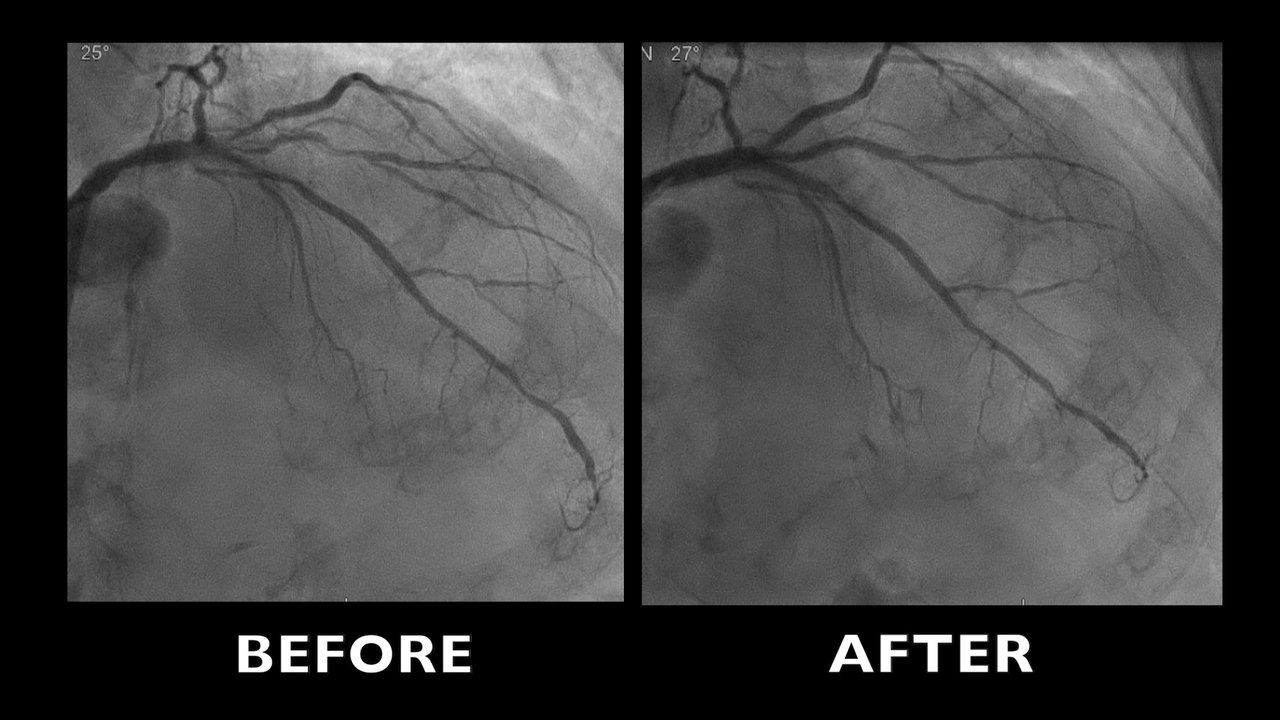

Multi vessel disease in left artery, complex stenosis of distal LMCA and proximal LAD with stenosis in trifurcation in both diagonals and a short circumflex artery.

A good angiographic result at the end of the procedure with Stentboost